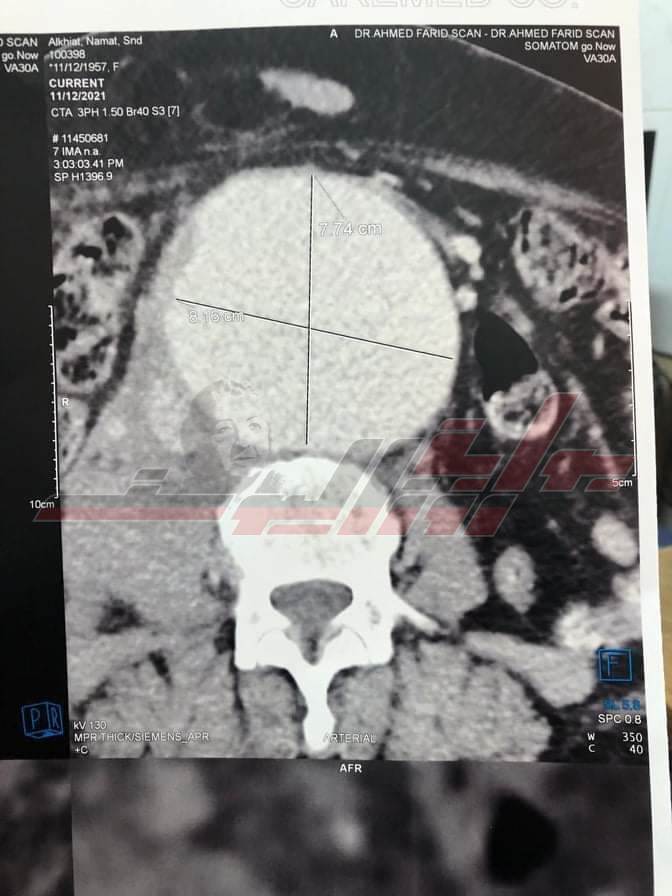

نجح الفريق الطبي بوحدة القسطرة التداخلية الطرفية بمستشفيات جامعة بنها، فى تركيب دعامة مغطاة لمريضة عمرها 61 عاما، تعانى من تمدد بالشريان الأورطي البطينى ذات حجم كبير وبه تسريب دموي، مما يصعب من عملية التدخل الجراحى، نظرا لصعوبة الحالة وتقدم المريضة فى العمر.

وتم إجراء عملية القسطرة للمريضة وحالتها الصحية جيدة ومستقرة، تم التشخيص بواسطة جهاز الأشعة المقطعية ١٢٨ متعدد المقاطع الخاص بالشرايين التاجية بقسم الأشعة بمستشفيات جامعة بنها.